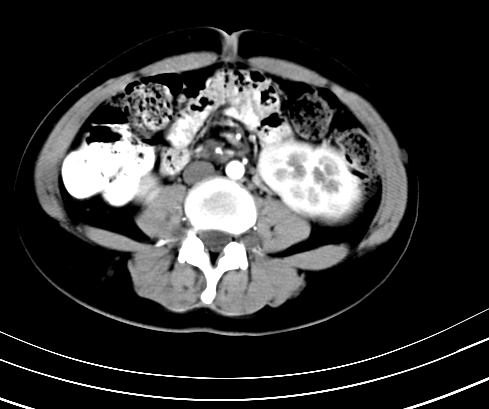

动脉期

静脉期

神经纤维瘤病

支持 神经纤维瘤病。